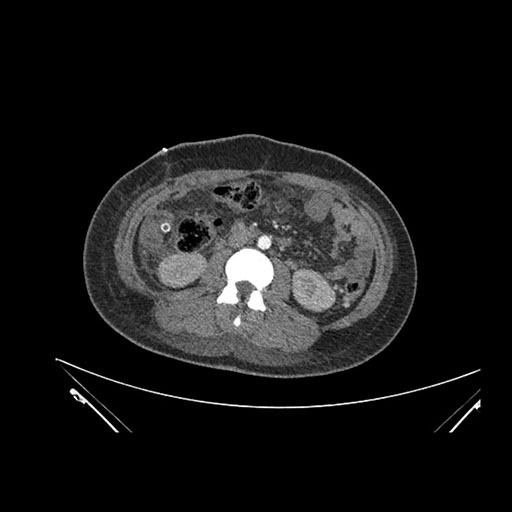

Axial Arterial